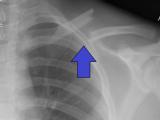

Новое исследование, представленное в Journal of the Endocrine Society, показало насколько эффективным может быть искусственный интеллект (ИИ) в чтении электронных радиологических снимков. В частности, система смогла...